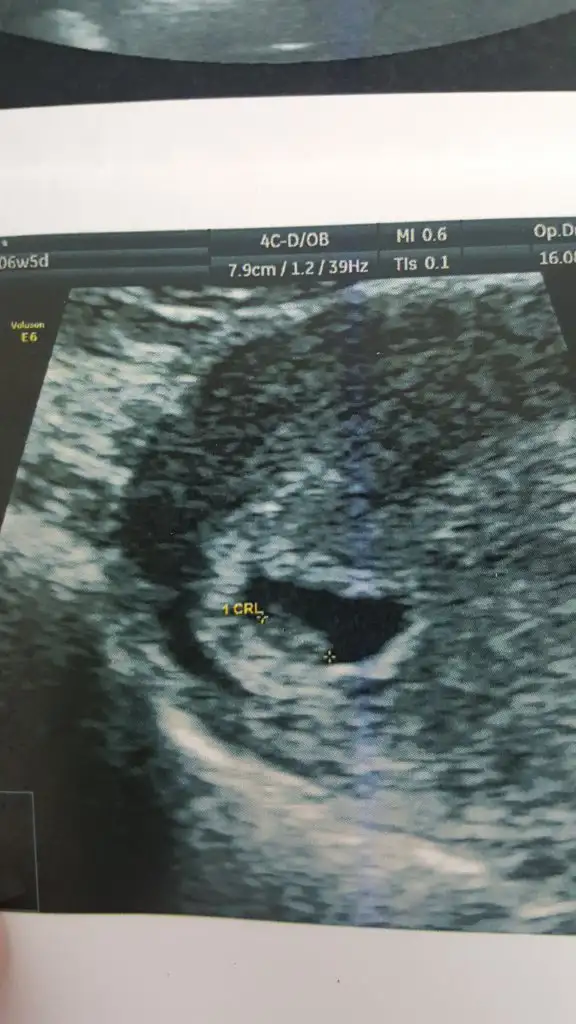

Ultrasonda bebeğin gözüktüğü resmî istiyorsanız yuvarlak değildi 7 haftalık ilken bu şekilde idi